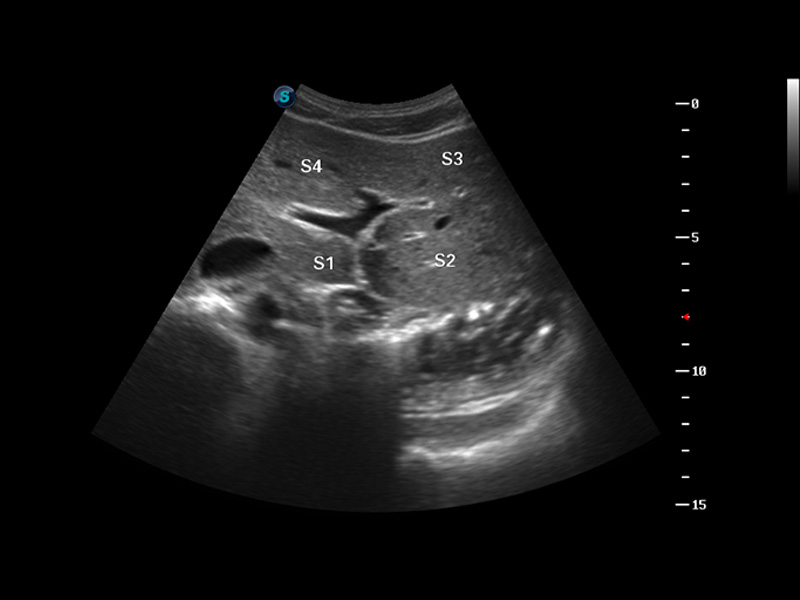

S8 EXP便携式彩色多普勒超声诊断仪是狗万官方网站研发的高端全身应用型便携彩超。高通道的VIS平台融合可视化(Visual)、智能化(Intelligent)和人性化(Smart)的特点,配以狗万官方网站自主研发生产的探头大家族,使您能够快速、准确的获得病人信息,提高工作效率的同时减轻疲劳。

μ-Scan微米成像